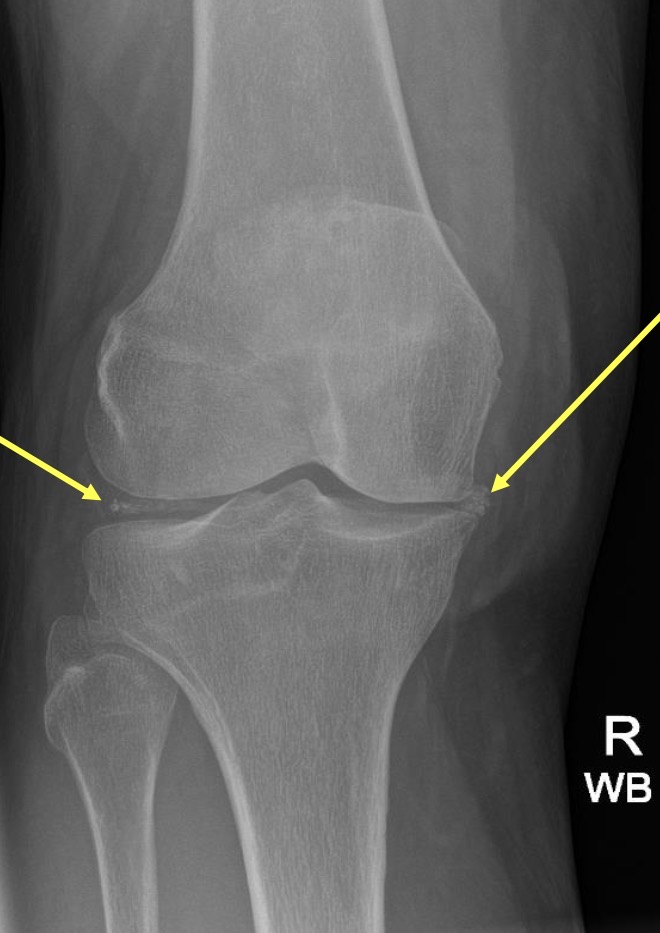

Calcium Pyrophosphate Deposition (CPPD) ⭐

Also known as pseudogout

Calcium deposit within the joint

State it as ‘Calcium deposition within the joint space consistent with CPPD or pseudogout’